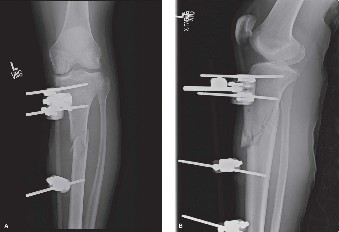

A 43-year-old male presents to the emergency department after falling approximately 15 ft while trimming tree…